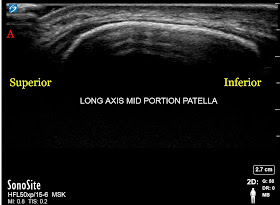

Getting back to the 13 year old baseball player, based on his age and pain near the patella, I was anticipating that he may have SLJ syndrome. However, his pain was located higher (on the superolateral portion of his knee cap).

Indeed, as the image below shows, the patella looked pristine in the center, with a smooth cortex